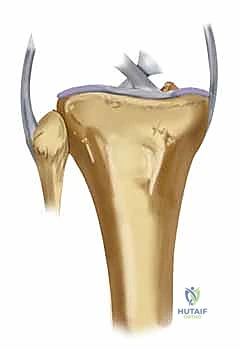

- الكسور المرتبطة بشظايا خلفية إنسية (Posteromedial Fragments): يجب دائمًا التمييز بين الكسور الوحشية التي تترافق مع شظايا خلفية إنسية. هذه الشظايا حاسمة جدًا، حيث تتطلب غالبًا نهج تثبيت خلفي إنسي مخصص، ومستقل عن التثبيت الوحشي. إن إغفال تثبيت هذه الشظايا يؤدي حتمًا إلى انزلاق المفصل للخلف وفشل العملية.

2. الشقوق الجراحية (النهج المزدوج - Dual Incision Approach)

لأن الكسر يشمل الجانبين الإنسي والوحشي، فإن شقًا جراحيًا واحدًا لا يكفي. يقوم الدكتور هطيف عادة بعمل شقين منفصلين لضمان عدم سلخ مساحة كبيرة من الجلد وتقليل خطر النخر:

* شق أمامي وحشي (Anterolateral Incision): للوصول إلى اللقمة الوحشية (التي تكون غالبًا مفتتة ومنخسفة).

* شق خلفي إنسي (Posteromedial Incision): للوصول إلى اللقمة الإنسية الك